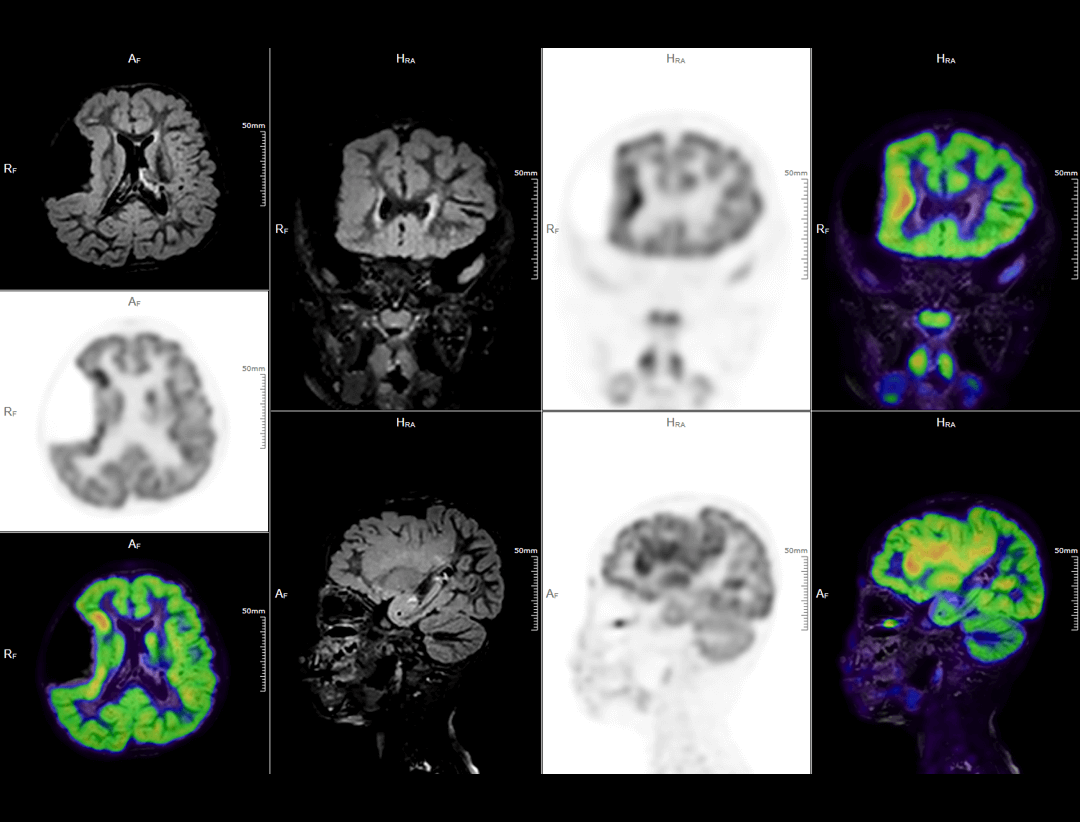

神经成像

得益于时空一体平台,uPMR 790开启行业技术先河,深度挖掘原始融合数据信息,为高级脑功能研究、运动伪影校正、肿瘤影像组学、转化医学等前沿科学研究提供无限可能,开启PET/MR科研新篇章。

• uPMR 790具有软组织分辨率好、多参数多序列成像、同时行功能性检查、无电离辐射等多项优势。同时,还可做到PET与MR信号同时采集,从而实现最佳的影像表现与功能信息显示,在全身疾病诊疗中的优势日益彰显。